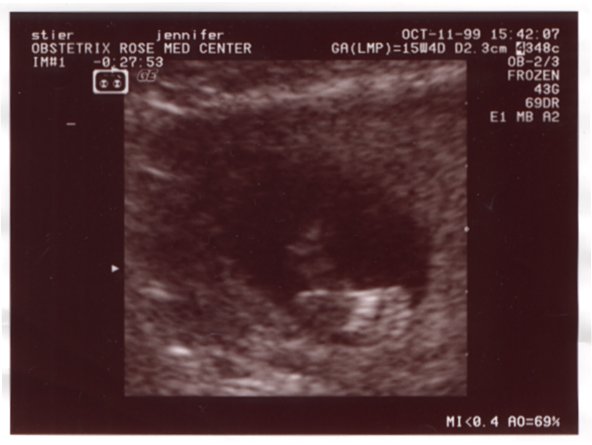

Ultrasound Picture No. 2